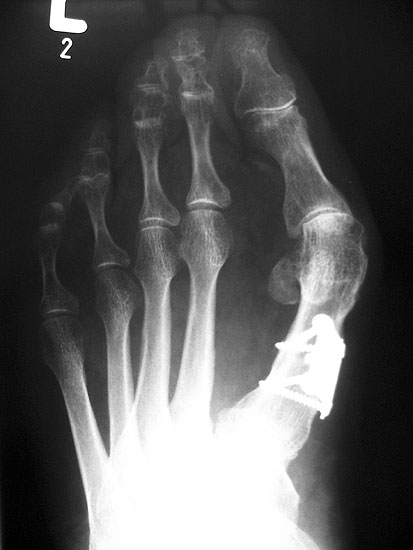

1) Arthrodese Großzehengrundgelenk

Schlüssel für eine erfolgreiche Arthrodese am Großzehengrundgelenk ist die exakte Stellung der Zehe. Eine freie Beweglichkeit im Interphalangealgelenk sollte vorhanden sein, die Grundphalanx sollte den Abrollvorgang nicht behindern und gleichzeitig dorsal nicht im Schuh scheuern. Es ist anzustreben, dass bei Flexion im Interphalangealgelenk die Großzehenbeere den Boden erreicht.

Arthrodese Metatarsophalangealgelenk

Die Häufigkeit einer Pseudarthrose nach Arthrodese am Großzehengrundgelenk wird in der Literatur mit  bis zu 20% angegeben, die meisten Autoren berichten aber über Werte zwischen 5 und 10% 3536. Bisher gibt es keine Evidenz, dass Platten bezüglich der Pseudarthroserate bessere Ergebnisse liefern als gekreuzte Schrauben. Die dreidimensional geformten Platten erleichtern allerdings die korrekte Positionierung der Zehe, aufgrund ihrer leichten Valgus- und Dorsalstellung.

Die Prinzipien der Pseudarthrosenbehandlung sind analog der Hallux valgus Korrektur anzuwenden (siehe oben). Die größere Herausforderung im medizinischen Alltag sind allerdings Patienten, die aufgrund einer nicht idealen Stellung des Gelenks über anhaltende Beschwerden klagen. Nach einer Arthrodese kann die Großzehe im Schuh nicht ausweichen. Bei zu geringer Valgusstellung kommt es häufig zu rezidivierenden Entzündungen des medialen Nagelfalz. Meist läßt sich die Situation durch ausreichend weites Schuhwerk beherrschen, ansonsten ist die Indikation zur Stellungskorrektur gegeben.